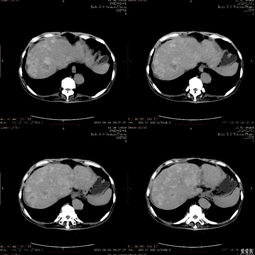

肝癌-乙肝携带者多年不复查,肚子胀发现肝癌破裂出血

引言:被忽视的“小毛病”与致命的转折 在快节奏的现代生活中,许多人都背负着健康“历史问题”前行,其中慢性乙型肝炎病毒(HBV)携带者是一个庞大的群体。对于部分携带者而言,由于早期可能没有明显症状,加之对疾病进展的轻视或对长期服药的顾虑,定期复查常常被置于次要位置,甚至被完全遗忘。肝脏是一个“沉默的器官”,当其内的隐患悄然滋长、最终爆发时,往往已酿成无法挽回的...